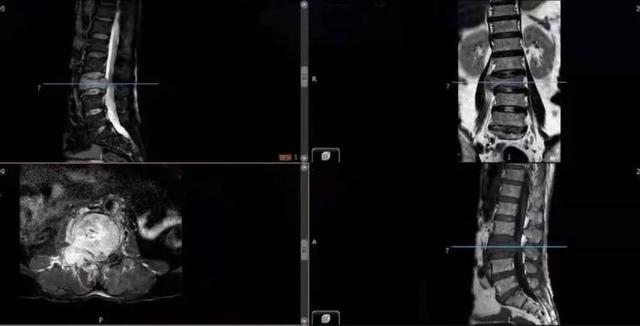

△MRI显示:L3椎体被肿瘤完全破坏,右侧神经受压明显。